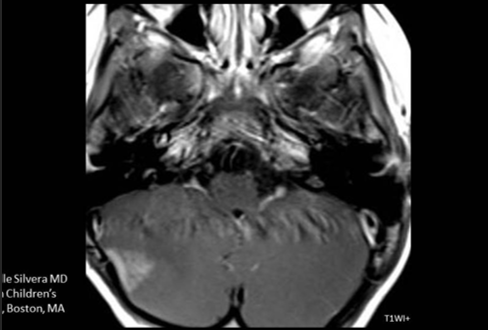

A 3-year-old child is admitted to the hospital due to decreased appetite and weight loss. She has been afebrile, and has not had vomiting or diarrhea.

Her activity level has decreased over the past two weeks.

She had been healthy until 2 months ago, when she was hospitalized for 48 ...

infection with mild respiratory distress and poor fluid intake.